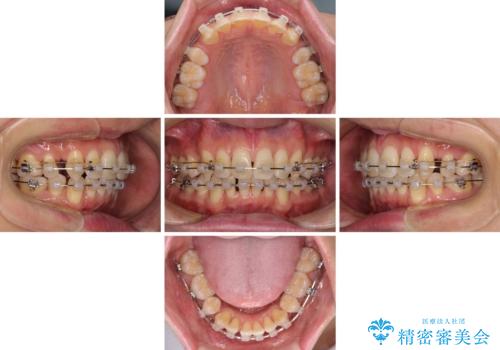

- クリアブラケット

- 治療期間

- 2年

叢生が強い場合、抜歯スペースが叢生を解消するために消費されるため、口元の突出感があまり改善されないことがあります。

今回の治療では、奥歯が前方に傾斜した歯並びだったため、奥に起き上がることで歯列が後方に移動し、横側からも口元が引っ込んだ感じが分かるほど改善されました。